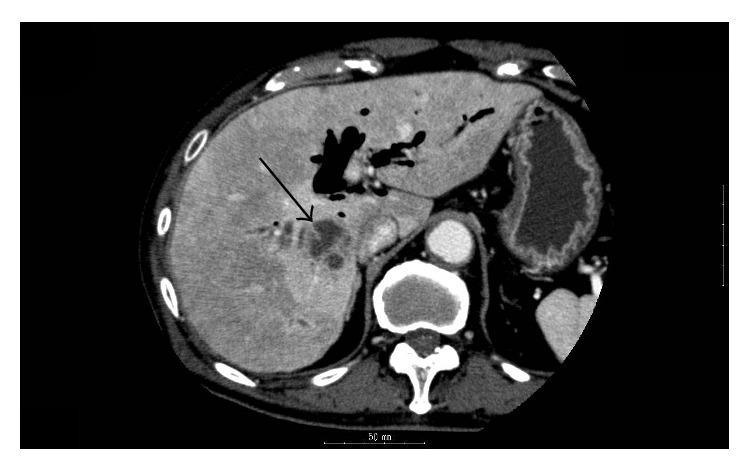

A Case of Liver Abscess with Desulfovibrio desulfuricans Bacteremia.

Desulfovibrio spp. are gram-negative, sulfate-reducing, and anaerobic bacteria found in the digestive tract of humans. Because Desulfovibrio spp. are infrequent causative agents of infectious diseases and are difficult to isolate and to identify from clinical specimens, the appropriate antibiotic therapy to infection with Desulfovibrio spp. has not been determined. We report the first case of liver abscess with bacteremia due to Desulfovibrio desulfuricans to show the clinical presentation and treatment. The patient was successfully treated with intravenous piperacillin-tazobactam and oral amoxicillin-clavulanic acid.